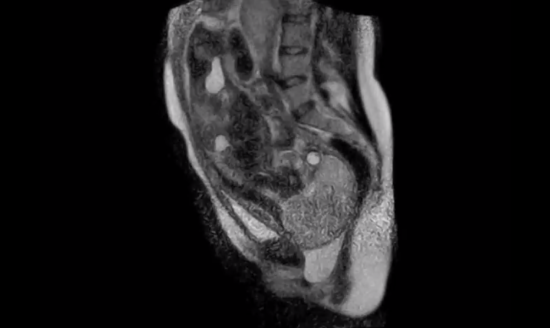

The team at Charité University Hospital in Berlin developed new fetal monitoring equipment to withstand the magnetic fields in the MRI. The video is composed by joining the repeated images taken by the MRI of the same cross-section of the body, a technique called cinematic MRI. Naturally, this technology is not developed for the Internet’s viewing pleasure, but for improving techniques during labor and delivery. Being able to see inside the body would make it easier for doctors to see what’s going on, and to better prepare for complications.

The video shows the second stage of labor, a stage awesomely called the “fetal expulsion stage.” Look at those eyeballs staring. Staring.